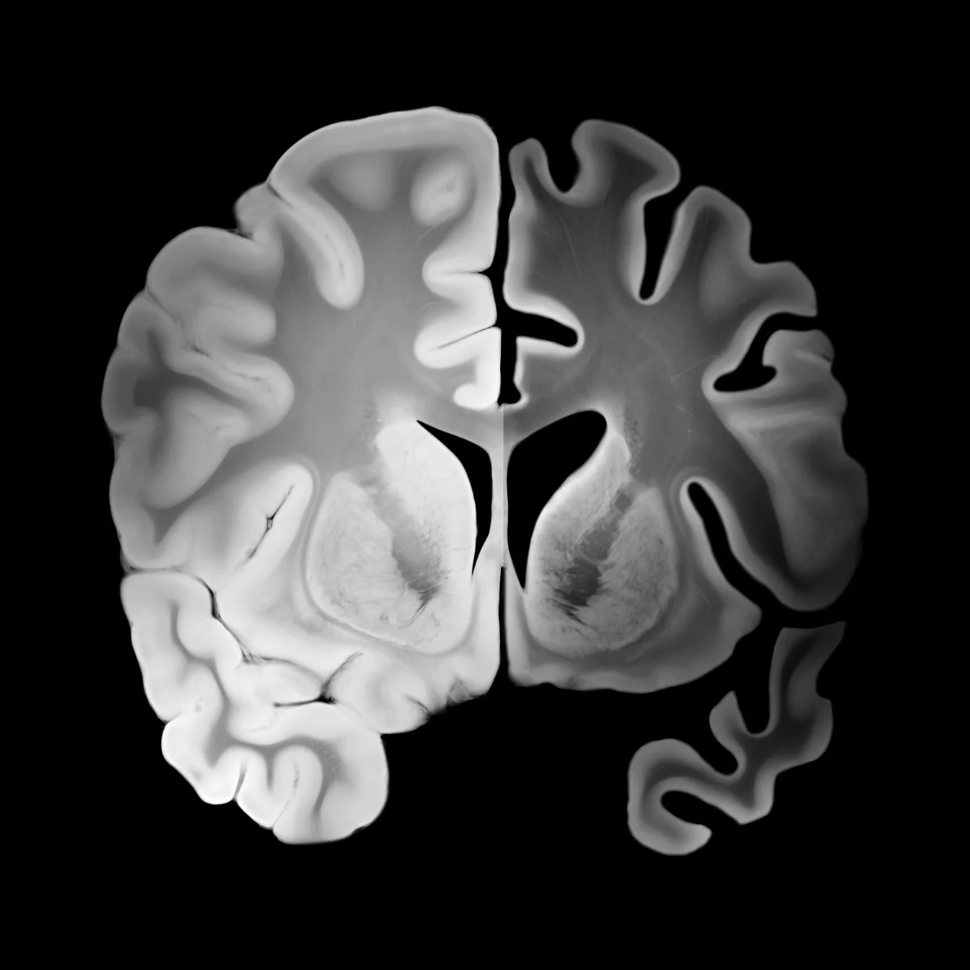

Alzheimer’s disease is defined by hallmark pathologies such as amyloid plaques, tau tangles, inflammation, and neuron loss. Once neurons die, the prevailing belief has been that the damage is permanent. Most therapies have therefore aimed to slow further degeneration rather than restore brain function.

Recent research, however, reframes Alzheimer’s as a disease of metabolic collapse, not just protein accumulation.